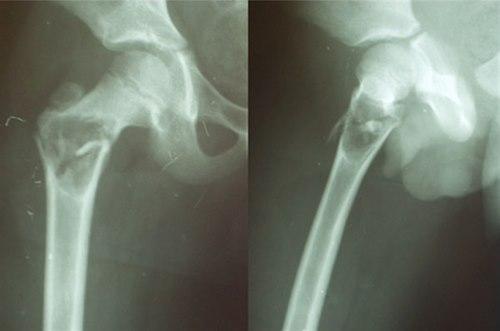

Diagnosen stilles ved røntgen som viser typiske funn, en cyste som omfatter det meste av diameteren til beinet, kun omgitt av en tynn beinet kant. CT eller MR er sjelden påkrevd.